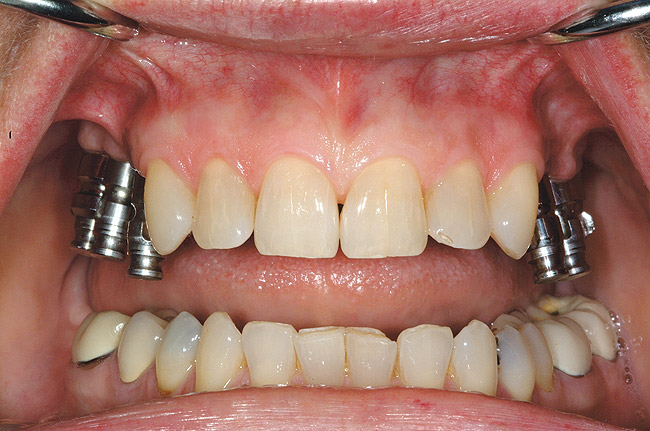

Figure 5  Locator abutments placed on implants can also be used for an implant-assisted prosthesis.

Figure 5

When dental implants were introduced by Brånemark, they were intended primarily for the completely edentulous patient, specifically the edentulous mandible. The initial prosthesis was a fixed restoration commonly referred to as a fixed bone anchored bridge. That particular prosthetic design is now the fixed-detachable hybrid prosthesis and has been highly successful for both the implants and prostheses.12,13 Implants have also been used for overdenture restorations14 and can be implant-assisted or implant-supported. With implant-assisted prostheses, the implants and mucoperiosteum share the forces of occlusion. A simple two-implant overdenture, either a Hader Bar® (Sterngold™, Attleboro, MA) or Locator® abutment (Zest Anchors, Escondido, CA), are examples of implant-assisted overlay prostheses and are always a removable restoration (Figure 4 and Figure 5). With implant-supported prostheses, the forces of occlusion are borne solely by the implants. This prosthesis can be an overlay prosthesis or a fixed restoration. Milled bar restorations, overdentures with bar substructures, and metal ceramic restorations attached to implant abutments by either screws or cement are examples of implant-supported restorations. One of the primary benefits of using dental implants in edentulous patients is the preservation of the residual bone, which will provide a better opportunity for future successful prosthetic restorations.